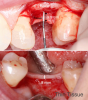

The crestal biologic interface, which includes vertical and horizontal bone and keratinized vertical soft tissue, represents an interface of the implant to the body (Figure 1). It is therefore essential to have a well-defined crestal biologic interface over the site at which the dental implant communicates with the oral cavity. The crestal biologic interface should have a minimum of 3 mm to 4 mm of vertical soft tissue supracrestally with a keratinized outer layer.8Once the implant has healed, it is desirable to have probing depths around dental implants that are 2.5 mm to 4 mm.

Fig 1. The crestal biologic interface: keratinized tissue, vertical junction epithelium, and the top of the connective tissue-xeal base abutment interface.

Figure 1